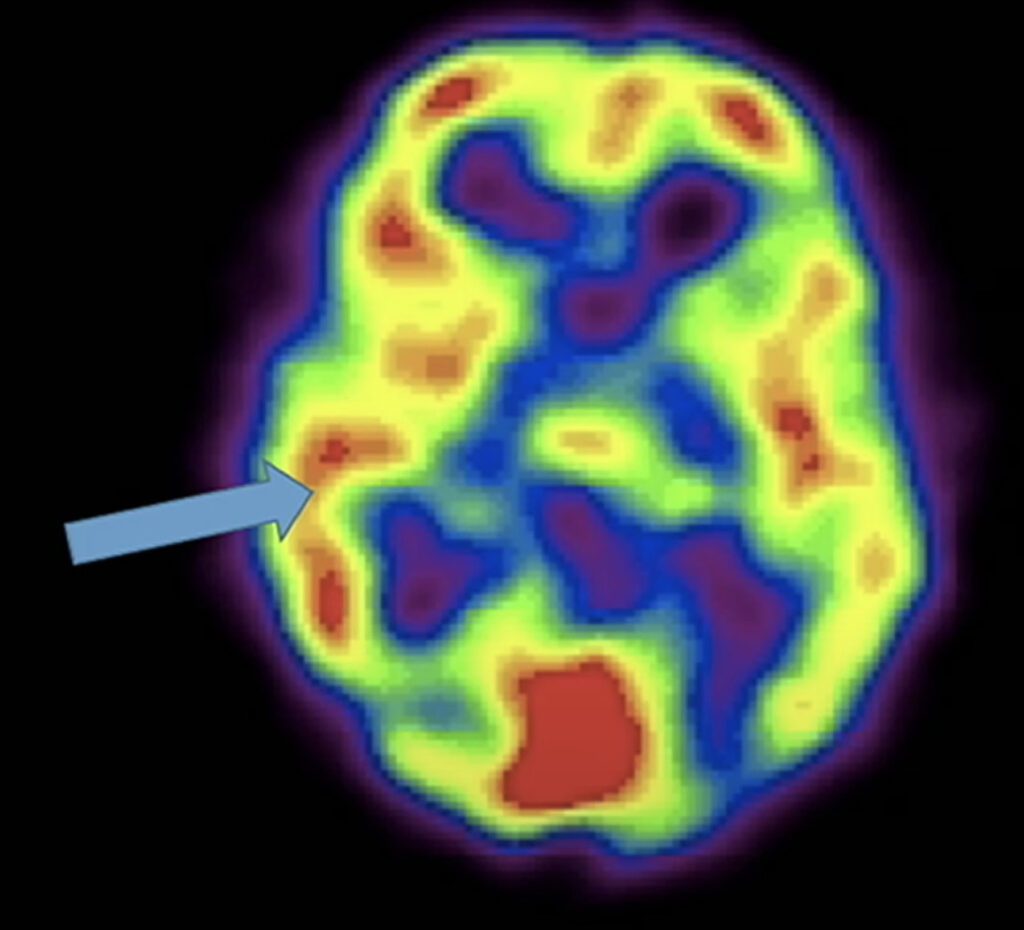

Newberg correlated fMRI brain scans with the study respondents’ descriptions of when they experienced a feeling of enlightenment or spiritual awakening during meditation. These scans showed increased blood flow and the firing of neurons in different parts of their brains. Newberg identified five core elements of the enlightenment experience.

The limbic area of the brain is the area of the brain that controls emotion. When something intense happens, this area will appear to fire up, turning red due to a rush of blood flow.

The brain scans of respondents that described this feeling of clarity showed one side of the thalamus lighting up and the other side going dark.

The thalamus is the center of the brain that takes our sensory information and constructs our view of reality.

Right behind your forehead is your frontal lobe. When you are concentrating, your frontal lobe turns on. The frontal lobe is the seat of the will. It’s what helps you make things happen. When the respondents felt a sense of surrender, the red area in their frontal lobe kind of melted away.

The brain scans of respondents that described this feeling of unity showed their parietal lobe area light up. The parietal lobe takes all of our sensory information and constructs a sense of self and our relation to the world. When you experience a profound sense of oneness and unity with the universe, the parietal lobe dims. The more it dims, the more the sense of self goes away, and the stronger the feeling of unity and oneness takes over.